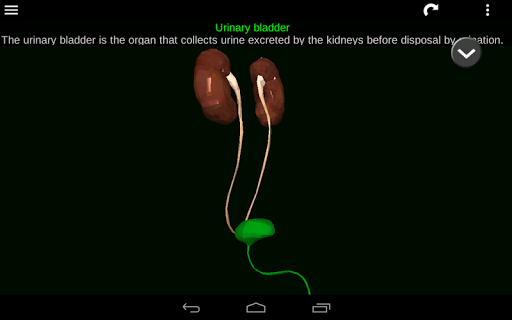

* Descriptions of each organ.